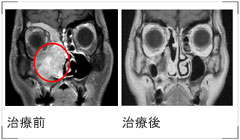

| ・治療前と治療後の画像と説明 |